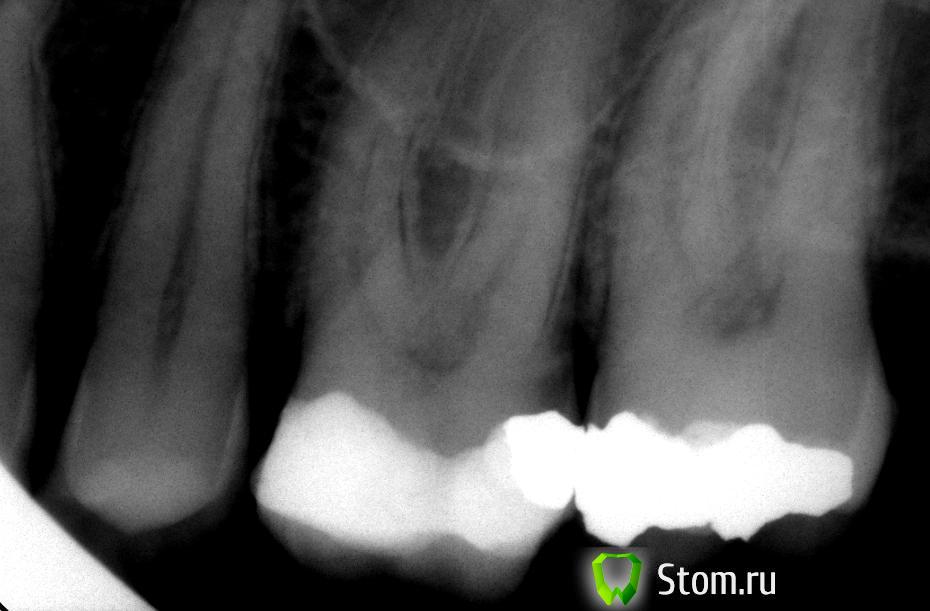

Ferny Опубликовано 27 февраля, 2012 Поделиться Опубликовано 27 февраля, 2012 Всем добрый день! Дайте пожалуйста ваши советы насчёт лечения зуба. Пациент 45 лет, зуб 26. Жалоба: когда кусает твёрдую пищу типа сухарей и попадает на 26 зуб то начинается боль, довольно острая, которая проходит в течение двух минут. Просто так зуб не болит. Перкуссия и пальпация безболезненная. Пломбу ставили по словам пациента очень давно, но боль появилась только месяц назад примерно. На рентгене большая пломба, но вроде не достаёт до пульпы. Коллеги на работе посоветовали депульпировать. на 27 зубе амальгама. Не знаю что делать с зубом. Сразу депульпировать ...или...ещё что то предпринять? Что Вы можете посоветовать? Спасибо! Ссылка на комментарий

Каплан Опубликовано 27 февраля, 2012 Поделиться Опубликовано 27 февраля, 2012 исключите трещину.дайте накусить валик ватный (или ватную палочку), если при открывании боль сильнее чем при накусывании - трещина в зубе... Ссылка на комментарий

3ухра Опубликовано 27 февраля, 2012 Поделиться Опубликовано 27 февраля, 2012 А кариеса на 2.6 нет? дистально. ЭОД есть? Поменяйте пломбу и посмотрите как оно будет. Ссылка на комментарий

Kivilgar Опубликовано 27 февраля, 2012 Поделиться Опубликовано 27 февраля, 2012 А кариеса на 2.6 нет? дистально. ЭОД есть? Поменяйте пломбу и посмотрите как оно будет.+1. Чем всякие страшные вещи предполагать, надо начать с самого простого. Может еще эмаль в каком-то месте стерлась и дентин чуть оголился и при сильном воздействии чувствует. Топикстартеру-что показало зондирование вокруг пломбы и что выявили при обследовании кармана? Ссылка на комментарий